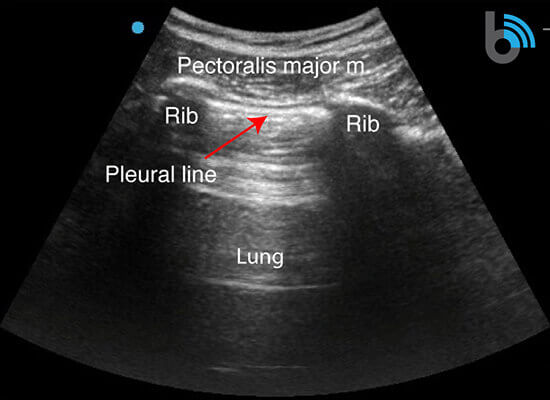

Anatomy

- The ribs will appear as convex hyperechoic lines with acoustic shadows.

- Located between the ribs are the hypoechoic intercostal muscles and the smooth, thin hyperechoic pleural line.

- These structures form the “bat sign”: the shadow of the ribs form the wings, while the area between the ribs represents the body.

Lung Sliding

- The pleural line is comprised of the parietal and visceral pleura, but will appear as a single, thin hyperechoic line.